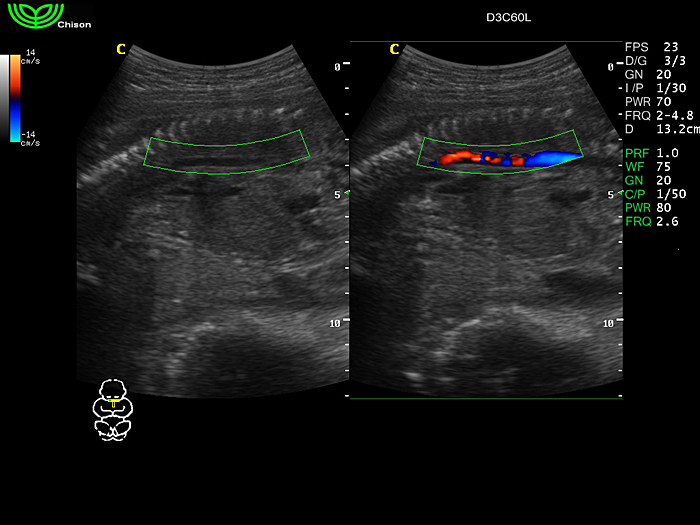

D3C60L 3.5МГц, конвексный.

2.0МГц - 5.8 МГц. Применения: абдомиальное обследование, акушерство, гинекология, обследование районной блокады нерва, осуществление и управление биопсией. |